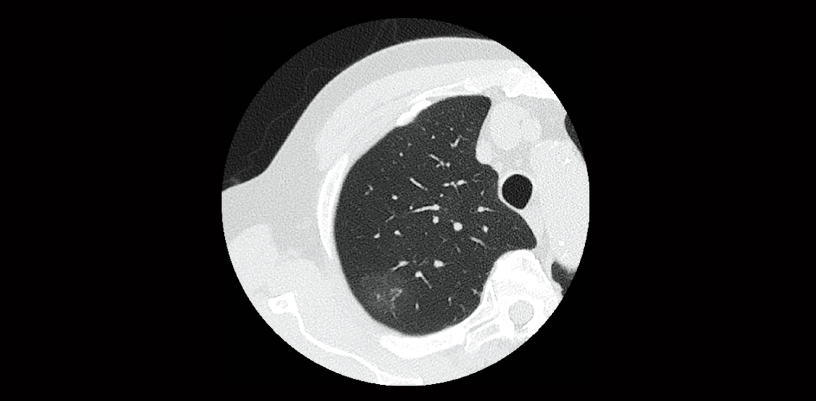

FBP(izquierda)

Intelli IPV(derecha)

Examen de detección pulmonar (vol. de CTDI: 2,0 mGy)